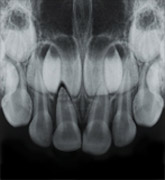

bitewing x-ray photograph X-Rays

Dental x-rays are special pictures taken of the insides of the teeth so that the dentist and hygienist may see if the person has cavities between the teeth. It is very important to get these pictures taken regularly because the dentist cannot see the sides of the teeth that touch. If a cavity is between the teeth and an x-ray picture is not taken, the dentist will not know if the cavity is there and cannot treat the cavity and stop it from growing larger. If the cavity is left to grow, it can become very painful.